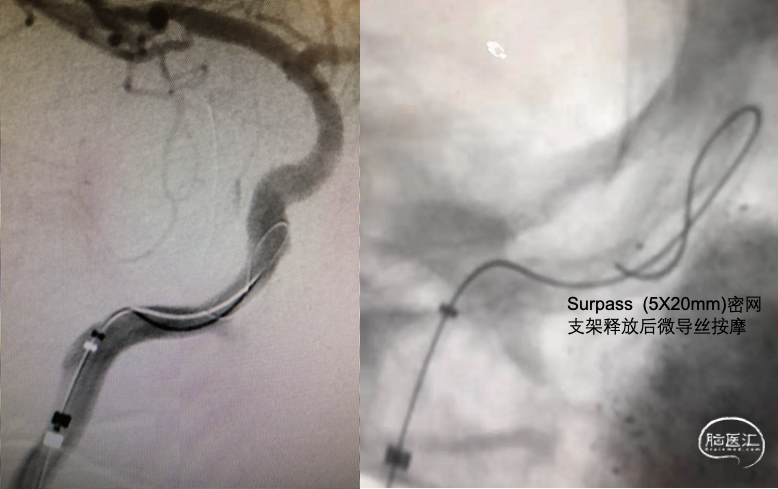

➤沿鞘送入常规泥鳅导丝(150cm 0.035”)带8F导引导管,将导管送至右侧颈内动脉C1段,撤出泥鳅导丝,在路径图下沿导引导管送入Synchro微导丝(0.014inX200cm)在微导管引导下将6F导引导管小心通过病变段至右侧颈内动脉C5段,撤出微导丝及微导管,在路径图下沿导引导管送入Synchro微导丝(0.014in长度200cm)带CAT5导管送至C5段,退出微导丝,沿CAT5导管送入Surpass(5X20mm)密网支架送至病变段,准确对位后成功释放支架。

➤Surpass密网支架释放后复查造影(2021-03-01)